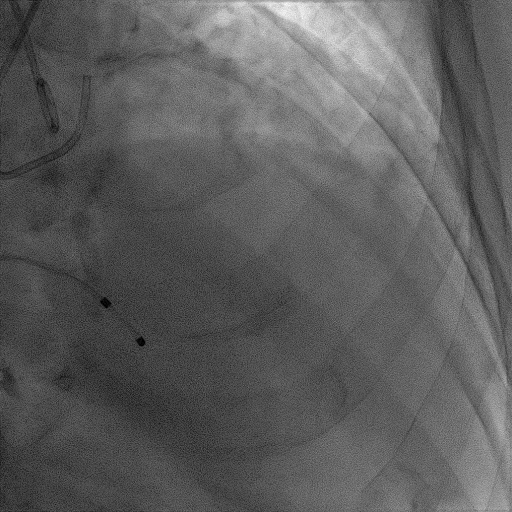

患者麻醉方式为全麻,建立静脉通路后,穿刺右侧股静脉,预埋ProGlide缝合器,食道超声指导下房间隔穿刺成功,将Superstiff导丝送至左房,应用18F鞘管扩张穿刺部位,沿导丝将导引导管送入左房,MitraClip调整后顺利到达二尖瓣目标位置,在X线及食道超声辅助下,将Mitraclip NTR成形夹精确定位后,成功夹合二尖瓣A2-P2区,超声显示反流明显减少,多切面证实夹合组织充分,肺静脉多普勒波形由反向恢复正常,手术顺利结束,安返普通病房。

术中超声

确定房间隔穿刺点:靠后

2D视图下测量大鞘长度2cm

3D视图打开夹子

X-plane:下第夹子尝试捕获2区

X-plane:测量前叶长25mm,后叶长14.2mm

X-plane:计算前叶捕获长度8mm,后叶捕获长度7mm

3D视图下观察二尖瓣双孔形态

3D-color:残余少量返流